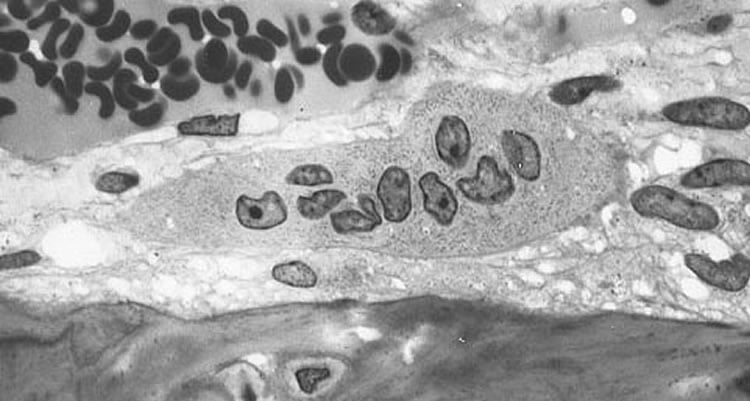

The researchers wanted to understand how donepezil prevents bone degradation. They looked at the drug’s activity in vitro using mouse bone marrow cells, and found that more acetylcholinesterase is produced when osteoclasts are being made, which leads to even more osteoclasts being made. Donepezil stops acetylcholinesterase from working, therefore preventing osteoclasts from being made.

The team also looked at the effect of the drug in a mouse model with bone loss. They found that donepezil increases bone mass in mice by preventing the production of osteoclasts.

Cell-based assays were conducted using osteoclasts generated in cultures of murine bone marrow macrophages (BMMs) with receptor activator of nuclear factor-kappa B ligand (RANKL). The effect of donepezil was also determined in vivo using a mouse model of RANKL-induced bone loss.

Recombinant AChE in BMMs cultured with RANKL further promoted RANKL-induced tartrate-resistant acid phosphatase (TRAP)-positive osteoclast differentiation. RANKL also upregulated AChE expression in BMMs. RNA interference-mediated knockdown of AChE significantly inhibited RANKL-induced osteoclast differentiation and suppressed gene expression specific for osteoclasts. AChE upregulated expression of RANK, the receptor of RANKL, in BMMs. Donepezil decreased cathepsin K expression in BMMs and the resorptive function of osteoclasts on dentine slices. Donepezil decreased RANK expression in BMMs, resulting in the inhibition of osteoclast differentiation with downregulation of c-Fos and upregulation of Id2. Moreover, administration of donepezil prevented RANKL-induced bone loss in vivo, which was associated with the inhibition of bone resorption by osteoclasts.